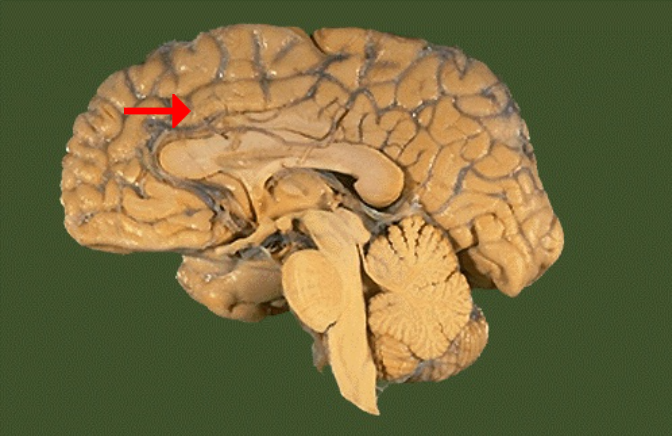

Label this brain structure

Cingulate gyrus

Name this brain structure

Fornix

Label this brain structure

Pineal gland

Label this brain structure

Sylvian fissure